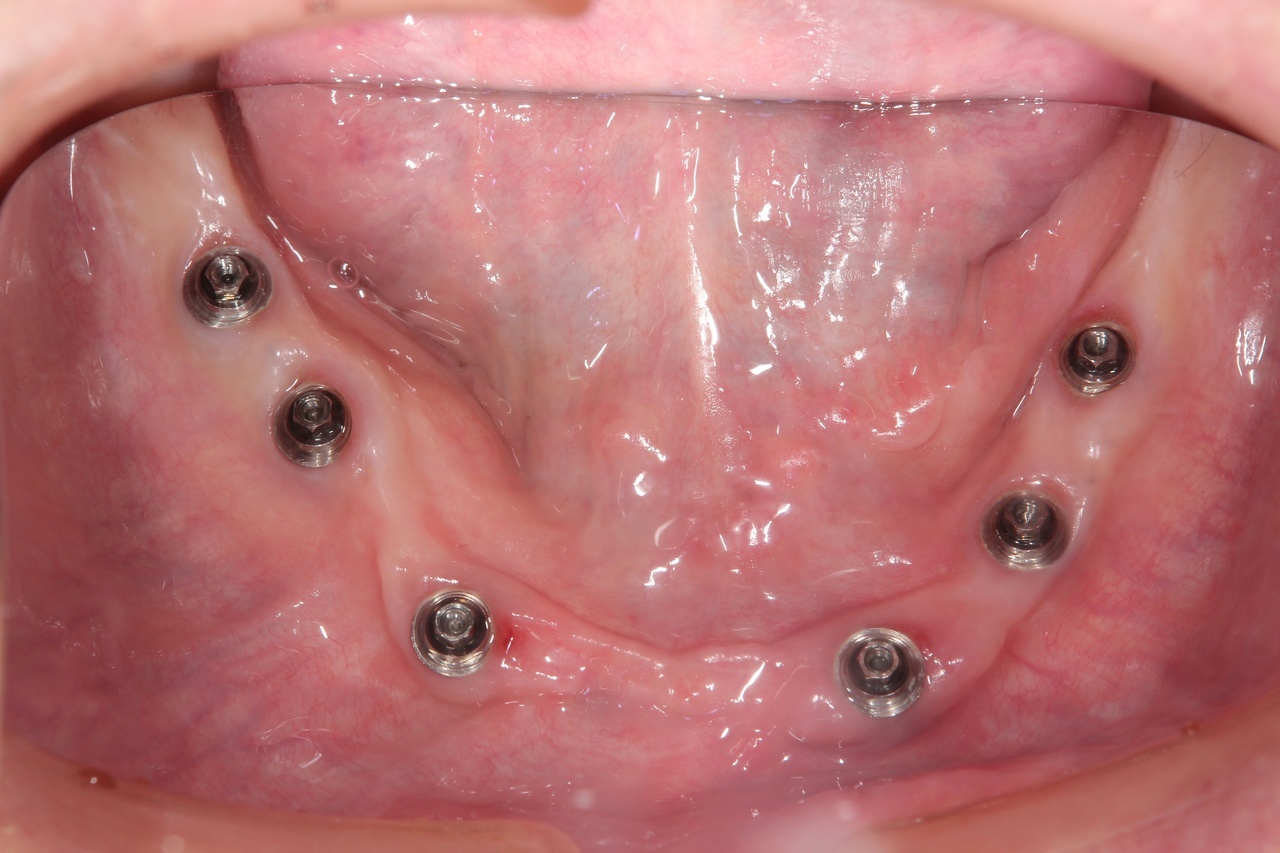

インプラントオーバーデンチャー<ロケータータイプ> (沼津市在住 男性)

インプラントを埋め込み、固定用のロケーターを装着し、入れ歯をしっかりと固定する治療法です。

少ない本数でがっちり噛める治療法です。取り外し可能でしっかり固定できるので、入れ歯の誤飲の心配がなく、手入れがしやすいので寝たきりになっても安心に使用出来ます。

しっかり噛むことで踏ん張りがきくので転んで骨折するリスク回避にもなります。

● オーバーデンチャーを外した状態

● オーバーデンチャーを付けた状態